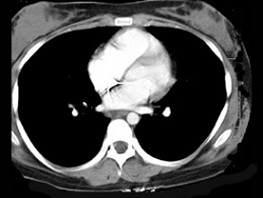

[单选题]7岁,男,发热、消瘦,数月前触及颈部淋巴结肿大,CT和MR检查如图,请选择最可能的诊断()A.淋巴瘤B.结节病C.淋巴结核D.转移性淋巴肿大E.胸腺瘤

[单选题]女,32岁,发热、消瘦,数月前触及颈部淋巴结肿大,CT和MR检查如图,最可能的诊断是()A .淋巴瘤B .结节病C .淋巴结核D .转移性淋巴肿大E .胸腺瘤